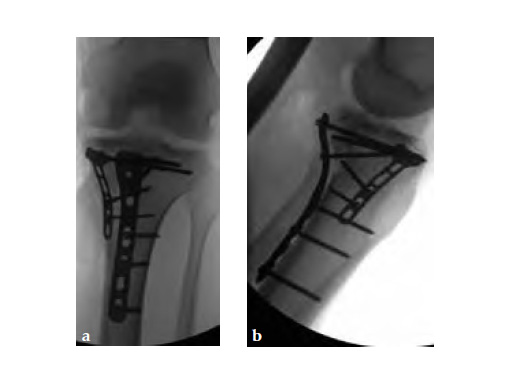

A 33-year-old male was involved in an altercation and suffered a gun shoot wound to his knee

Initially taken for incision and drainage and then ORIF . Patient placed in a floppy lateral position with the effected lower extremity externally rotated (opposite hip and shoulder bumped up about 3040) allowing exposure of the posterior medial knee. A posterior medial and an anteromedial incision were used to repair the fracture with a 67 cm skin bridge.

Postoperative healing was uneventful and the patient had no complications.